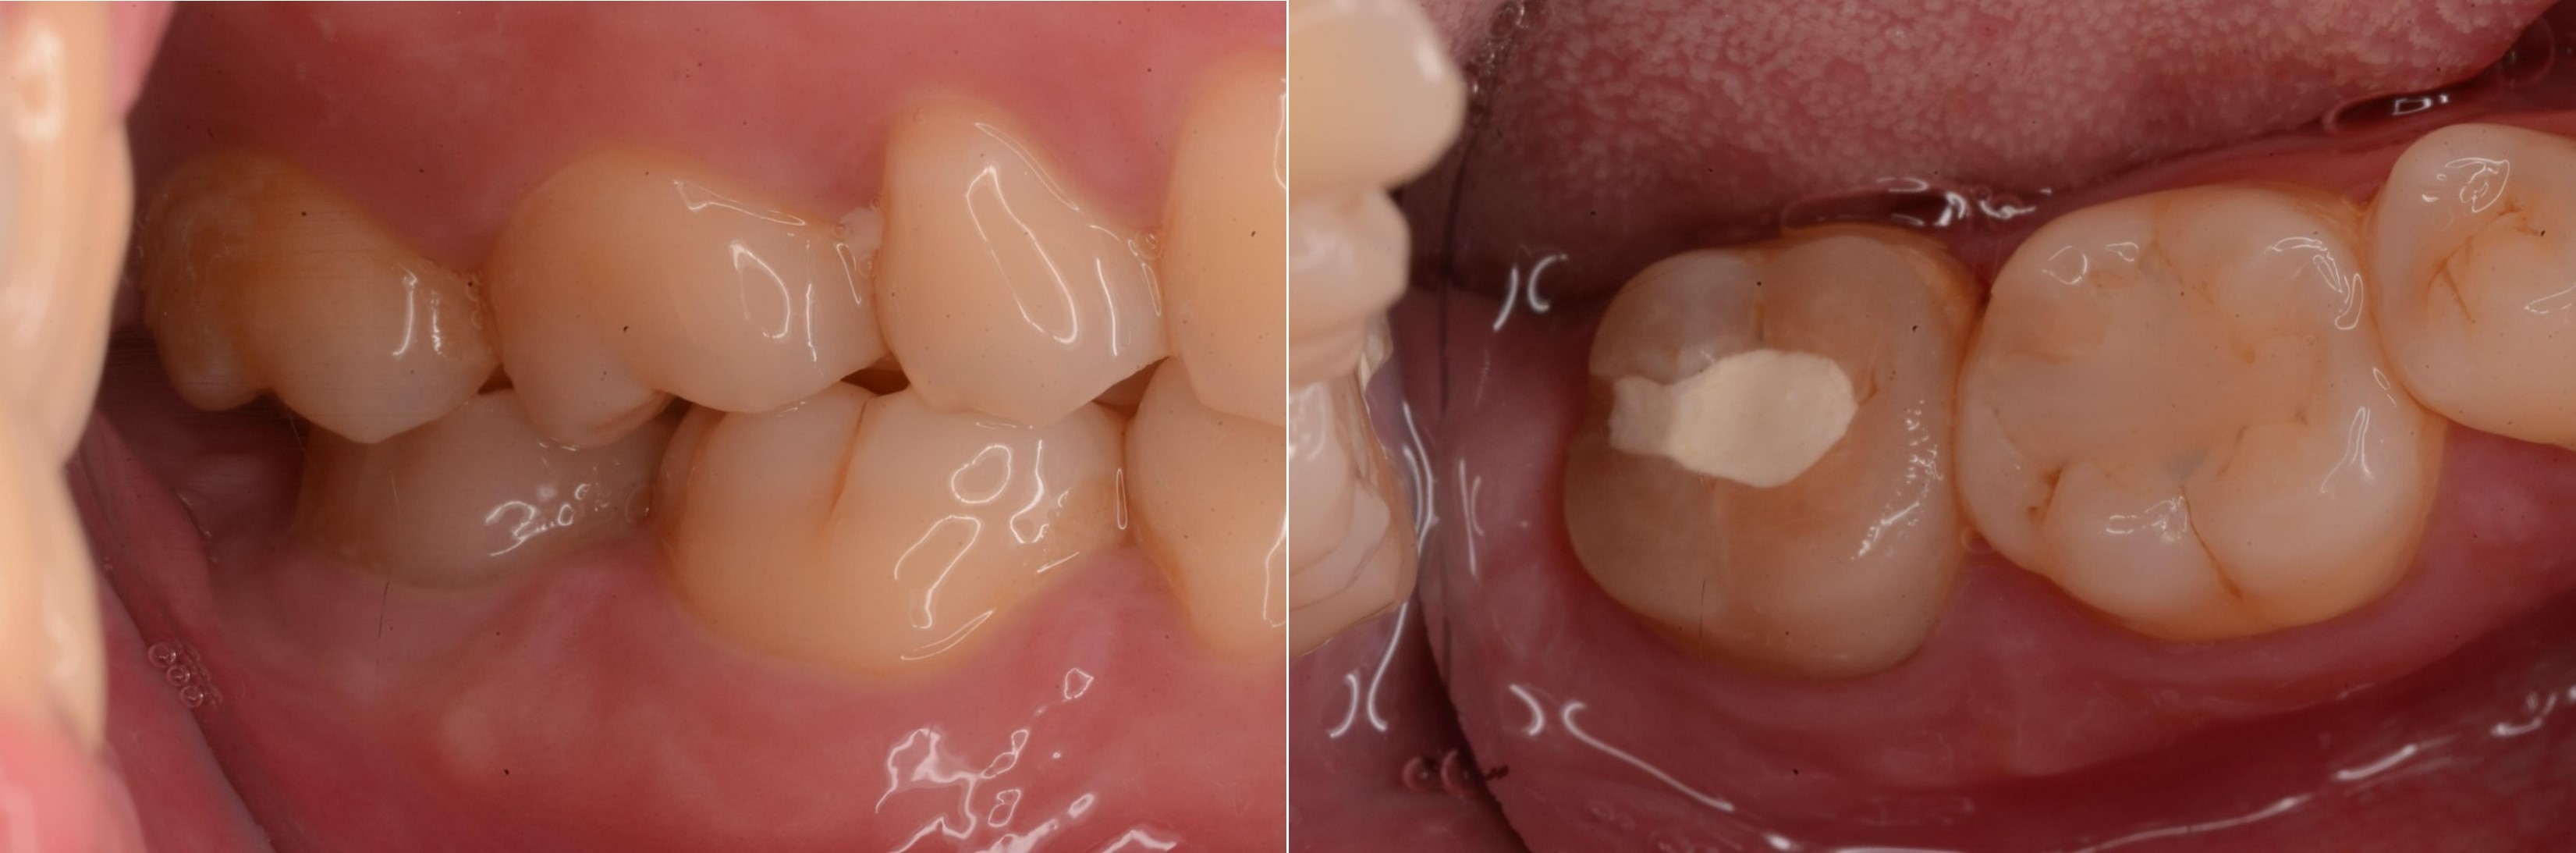

治療前,根管後大臼齒有牙裂

治療前,根管後第一大臼齒有牙裂